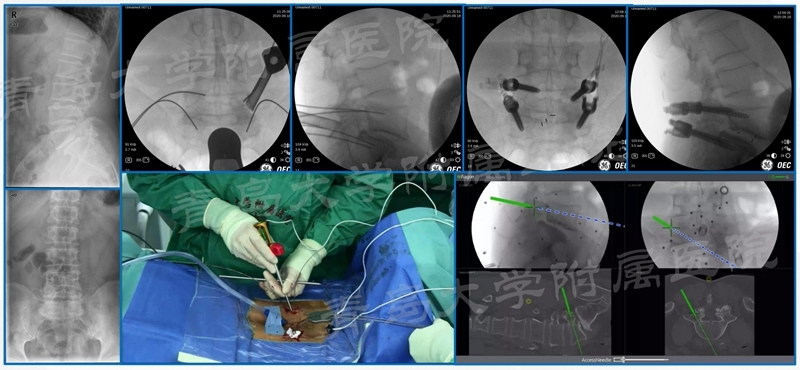

临床资料

回顾性分析了2019年7月至2022年4月期间52例术前或术后符合足下垂诊断标准的脊柱手术患者;记录患者平均年龄、术前诊断、发生足下垂的时间、手术方式、手术时间、住院时间、卧床时间及术后康复时间;患者随访至少24个月。术前、术后1周、术后3个月、6个月、12个月、术后24月分别评估SF-36、Oswestry残疾指数(ODI)评分及下肢肌力评定。

患者平均年龄48.1岁;52例出现足下垂;明确L5神经根受压者42例(80.8%)。术前即出现者28例(53.8%);26例恢复时间1周-2年;2例未恢复;术后神经功能加重9例(17.3%);1例1周恢复,2例1月,3例3月,1例24月;2例未能恢复。马尾综合征致足下垂者4例,1例未能完全恢复;术后血肿压迫者2例,术后1例1周恢复,另1例术后3月恢复;内镜手术后复发者1,术后10月恢复;开放腰椎术后2例,恢复时间6月;内固定者失败者2例,1例3月恢复,1例未恢复;术后各种原因致加重9+7=16例(30.8%);胸椎2例,平均恢复时间3月;颈椎1例,恢复时间6月。

典型案例

案例一

案例二

案例三

椎弓根螺钉进入椎管卡压L5神经根